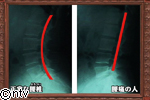

正常な腰椎というのは少し前に出ています。腰痛の人というのはそれがまっすぐになっています。これは、腰に負担がかかります。